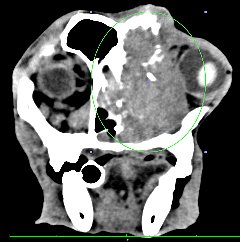

CT CT

本院では、4列マルチスライスヘリカルCT装置(TOSHIBA Asteion4)を導入しました。

1回転で4断面の画像を取得することができ,0.75秒の高速フルスキャンを可能とすることで,肺野領域30cmの範囲を最速6秒以下でスキャン可能です。

従来の1列のCTより短時間で、被爆量の少ない、正確な検査が可能です。

• 頭部病変

• 鼻腺癌による骨融解像 脳腫瘍

鼻腺癌による骨融解像 脳腫瘍